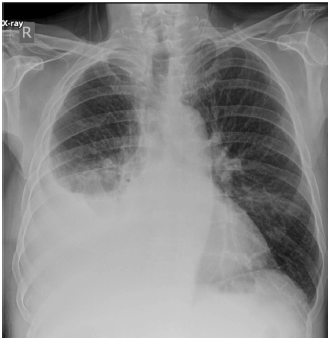

Paciente com 60 anos de idade, masculino, natural de Minas Gerais, procura consulta médica devido a um quadro de tosse crônica (início há 10 anos, aproximadamente), seca, associado à dispneia classificada como mMRC 2.

No interrogatório sintomatológico, não é apresentada mialgia, febre, perda ponderal, sudorese noturna ou chiado torácico.

Antecedentes pessoais: o paciente, em uso de losartana e sinvastatina, relata história de hipertensão arterial sistêmica edislipidemia, e nega história de tabagismo.

História ocupacional/exposições: o paciente relata que trabalhou por 20 anos na extração e beneficiamento de rochas, como granito e pedras preciosas, além de ter, eventualmente, prestado serviços em perfuração de poços.

No exame físico: verifica-se bom estado geral do paciente, orientado em tempo e espaço, com frequência cardíaca e respiratória sem alterações e saturação em ar ambiente de 94%.

Aparelho respiratório: sons respiratórios presentes e bilaterais, sem ruídos adventícios. Aparelho cardiovascular: ritmo cardíaco regular em dois tempos, sem sopros. Extremidades: sem edema, alterações de pele ou outras anormalidades notadas.

O paciente traz a seguinte radiografia de tórax:

Internet: < https://radiopaedia.org/cases/151132/studies/125463?lang=us >.

Considerando a principal hipótese diagnóstica do caso clínico hipotético apresentado anteriormente, julgue os itens a seguir.

I Indivíduos que têm esse diagnóstico apresentam até 3,5 vezes mais chances de ter tuberculose.

II Broncoscopia tem papel importante no diagnóstico, conseguindo, na maioria das vezes, fechar o diagnóstico.

III A espirometria, caso solicitada, poderia estar normal ou apresentar um espectro de padrões (obstrutivo, restritivo ou combinado).

IV O diagnóstico geralmente é clínico e baseado na história ocupacional, na imagem do tórax e na exclusão de outros diagnósticos possíveis.

V O tratamento é bem estabelecido e consiste em afastamento da exposição e uso de corticoide sistêmico, com remissão total das alterações na imagem e melhora clínica.

Assinale a opção correta.